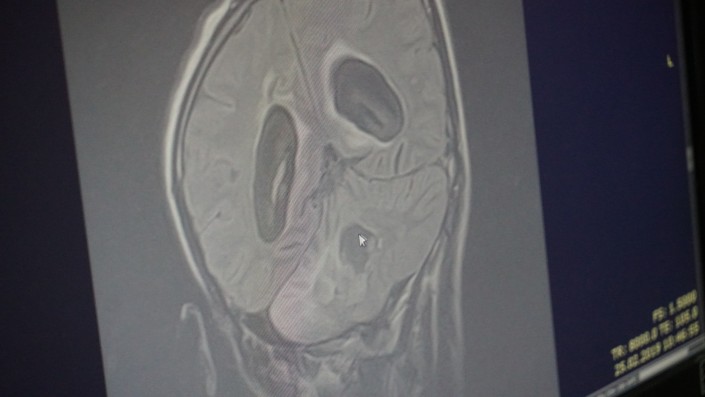

По совету соседа они сделали МРТ (магнитно-резонансная томография). Оказалось, что у парня опухоль головного мозга, и довольно внушительных размеров. Его сразу же отправили на экстренную операцию.